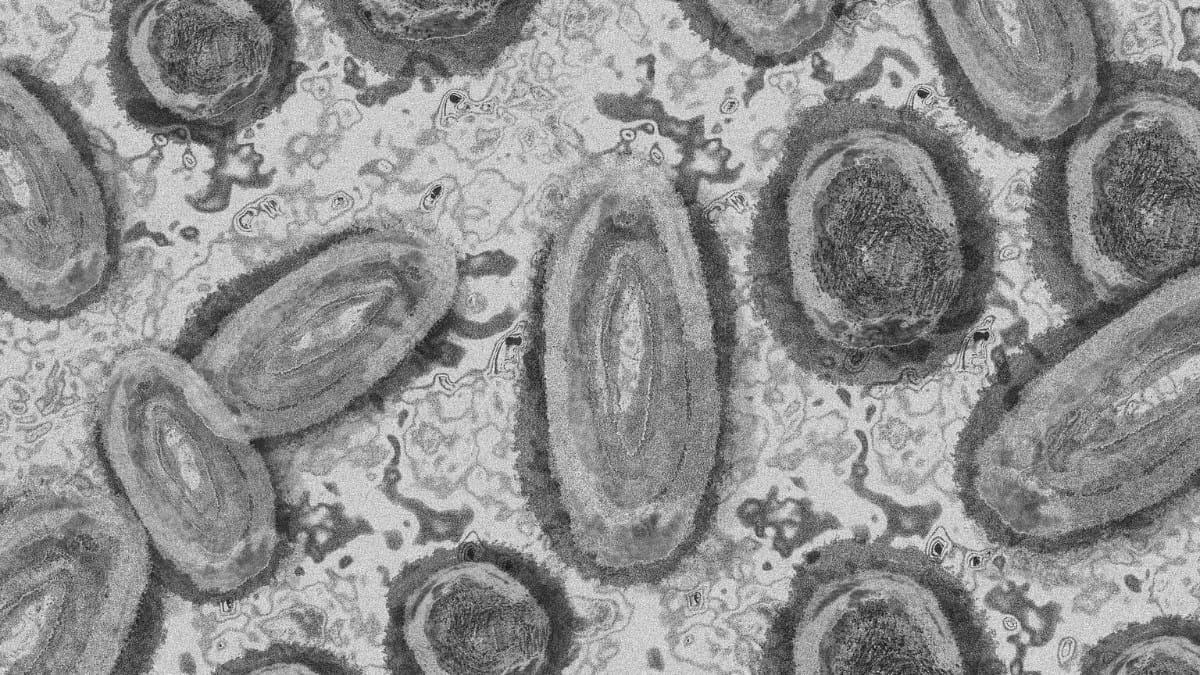

Em 2022, a mesma mulher, que não quis ser identificada, começou a ter esquecimentos, dificuldade de pensamento e depressão. Uma ressonância magnética revelou então uma “lesão atípica” no seu cérebro. Essa “lesão atípica” acabou por ser um verme de oito centímetros de comprimento, que ainda estava vivo.

O Hospital de Canberra e investigadores da Universidade Nacional Australiana (ANU) confirmaram que este foi o primeiro caso humano de Ophidascaris robertsi — nome do verme na senhora — descrito globalmente. As pítons-tapete são os hospedeiros comuns de Ophidascaris.

“Até onde sabemos, este é o primeiro caso a envolver o cérebro de qualquer mamífero, humano ou não”, declara o especialista principal em doenças infecciosas da ANU e do Hospital de Canberra e coautor do estudo, professor associado Sanjaya Senanayake.

Os investigadores concluíram que a mulher contraiu o parasita após colher folhas verdes de Warrigal, uma grama nativa. O parasita habita tipicamente o esófago e estômago das pítons, eliminando ovos nas fezes.